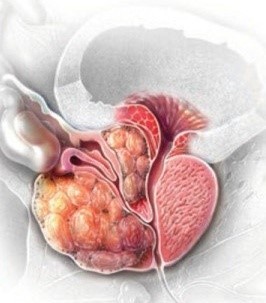

뼈나 관절계의 고통이 항상 전립선암을 나타내는 것은 아니긴 하지만, 가장 먼저 살펴봐야 할 증상 중 한가지인데요. 전립선암은 골반 림프절, 척추, 골반 뼈와 같은 전립선 주변 조직으로 전이되는 그럴 경우가 드물기 그리하여 이런 부위에 설명할 수 없는 고통이 있다면 의사와 상담하는 것이 중요해요. 일부 남자는은 허리, 엉덩이 또는 전립선 근처 부위에 고통을 느끼지만 단순한 신경통이나 관절통으로 치부하기도 해요.

골반 고통은 진행성 전립선암의 징후일 수 있어요. 고통은 일반적으로 옆구리, 배, 골반 부위에서 느껴지지만 암이 진행됨에 따라 뼈에서도 고통이 느껴질 수 있어요. 이런 부위에 고통이 있고 요로 감염 증상이 나타나면 의사를 내원해서 정확한 진단을 받는 것이 좋아요.